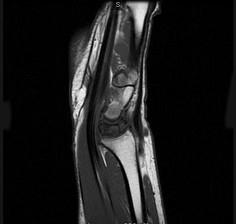

问题 女,41岁,纺织工,腕部痛无力数周,请结合CR和MR,选出最可能的诊断 ( )

选项 A、骨髓炎 B、骨软骨炎 C、月骨缺血坏死 D、骨质疏松 E、月骨结核

答案 C